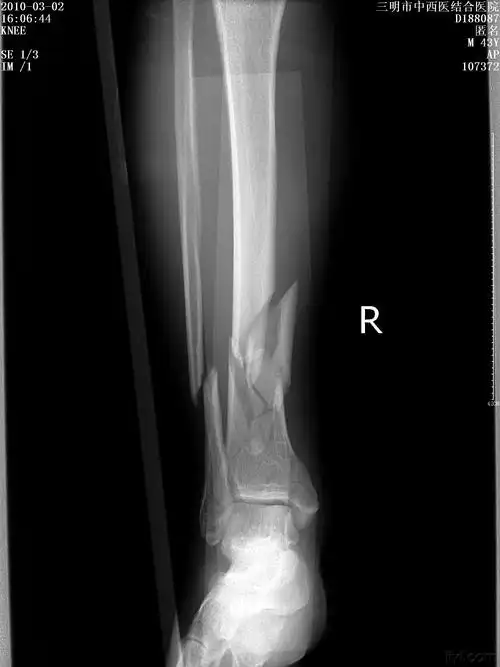

胫腓骨远端骨折